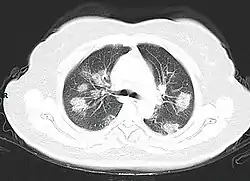

Imaging

Chest CT scans may be helpful to diagnose COVID-19 in individuals with a high clinical suspicion of infection but are not recommended for routine screening.[93][105] Bilateral multilobar ground-glass opacities with a peripheral, asymmetric, and posterior distribution are common in early infection.[93][106] Subpleural dominance, crazy paving (lobular septal thickening with variable alveolar filling), and consolidation may appear as the disease progresses.[93][107] Characteristic imaging features on chest radiographs and computed tomography (CT) of people who are symptomatic include asymmetric peripheral ground-glass opacities without pleural effusions.[108]

Many groups have created COVID-19 datasets that include imagery such as the Italian Radiological Society which has compiled an international online database of imaging findings for confirmed cases.[109] Due to overlap with other infections such as adenovirus, imaging without confirmation by rRT-PCR is of limited specificity in identifying COVID-19.[108] A large study in China compared chest CT results to PCR and demonstrated that though imaging is less specific for the infection, it is faster and more sensitive.[92]